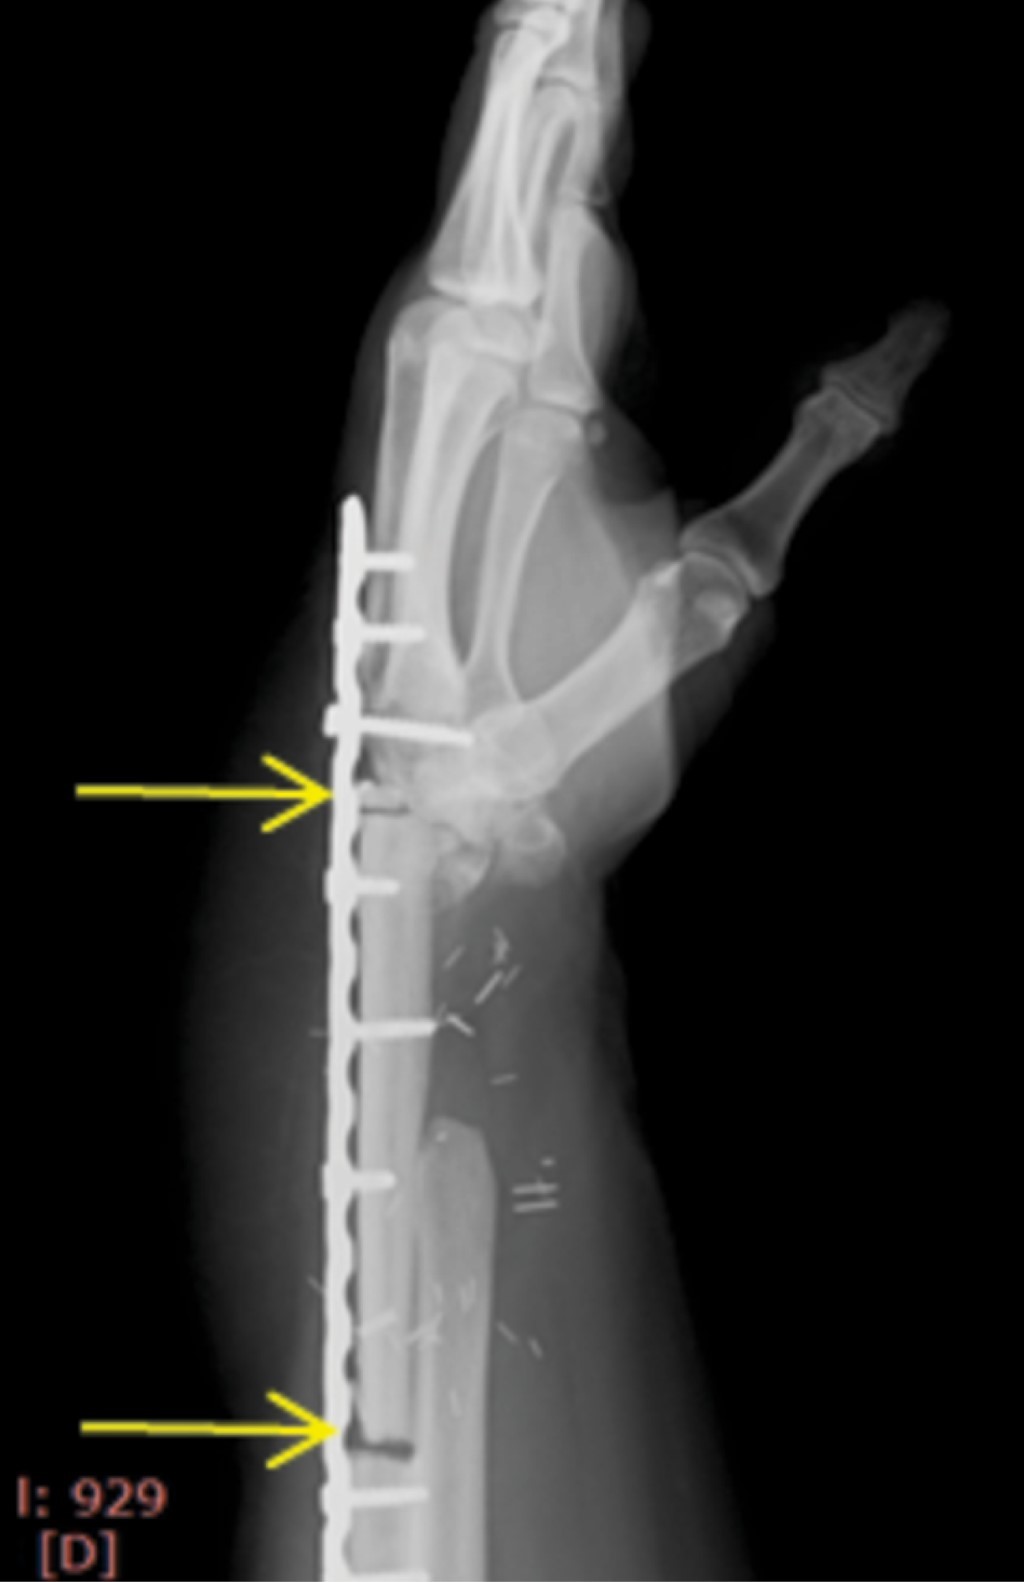

El seguimiento postoperatorio se llevó a cabo con controles radiográficos mensuales, se colocó una férula antebraquipalmar y se inició rehabilitación en la segunda semana. Sin embargo, al sexto mes persistía con dolor a nivel de la muñeca y el antebrazo, limitación funcional (pronación 90o, supinación -10o), debilidad (grip strength 50%, menor que el contralateral), con un puntaje DASH de 62.5, radiográficamente presentaba datos de no unión proximal y distalmente al peroné (Figura 4), misma que se decidió tratar de forma quirúrgica debido al tiempo de evolución.

Figura 4